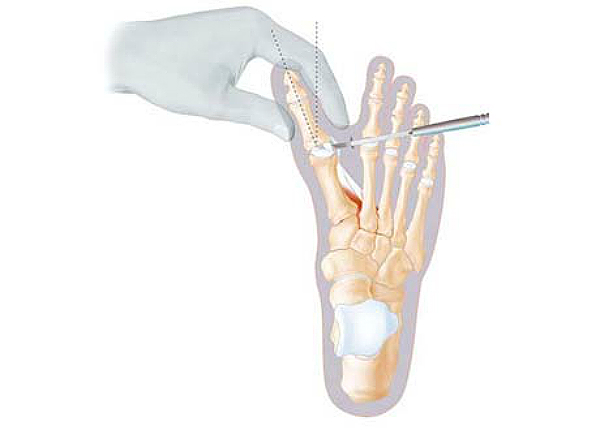

Рентген после операции Hallux valgus